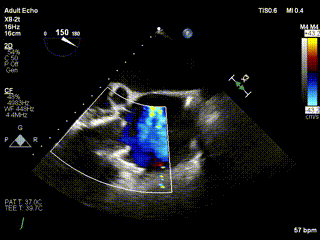

患者一术前心超

患者一术后心超